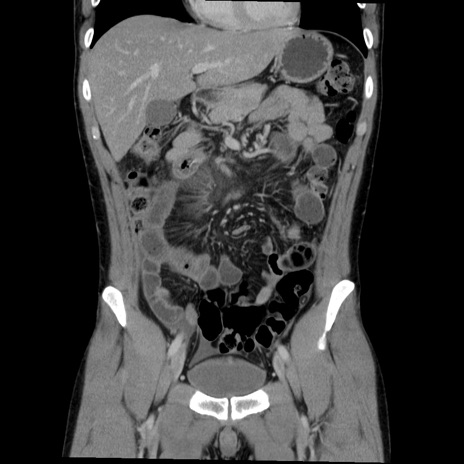

症例36(冠状断像)

【症例】20歳代 男性

【主訴】心窩部痛

【現病歴】今朝より上腹部痛あり。一旦軽快していたが再度出現したため救急要請。昨日夕に白身の魚を含む刺身を食べた。

【身体所見】BP 136/89mmHg、HR 74/min、BT 37.0℃、腹部:膨満、軟、心窩部に圧痛あり。反跳痛なし、筋性防御なし、腸雑音やや亢進あり。

【データ】WBC 17700、CRP 0.48